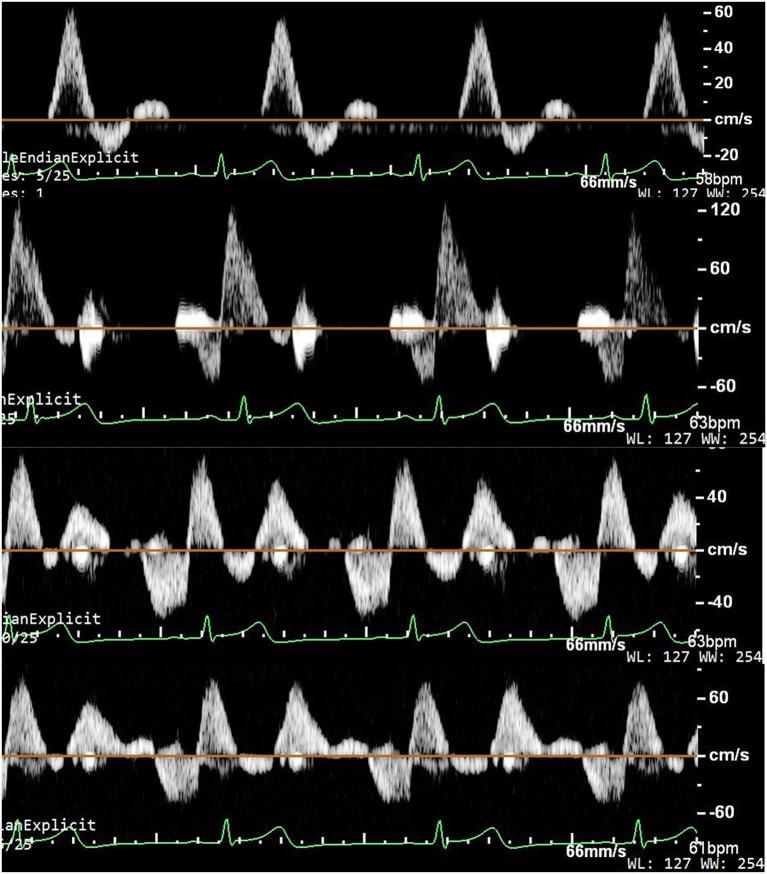

This study aimed to investigate acute hemodynamics of lower extremities during enhanced external counterpulsation with a three-level sequence at the hips, thighs, and calves (EECP-3), two-level sequence at the hips and thighs (EECP-2), and single leg three-level sequence (EECP-1). Twenty healthy volunteers were recruited in this study to receive a 45-min EECP intervention. Blood flow spectrums in the anterior tibial artery, posterior tibial artery, and dorsalis pedis artery were imaged by Color Doppler ultrasound. Mean flow rate (FR), area, pulsatility index (PI), peak systolic velocity (PSV), end-diastolic velocity (EDV), mean flow velocity (MV), and systolic maximum acceleration (CCAs) were sequentially measured and calculated at baseline during EECP-3, EECP-1, and EECP-2. During EECP-3, PI, PSV, and MV in the anterior tibial artery were significantly higher, while EDV was markedly lower during EECP-1, EECP-2, and baseline (all < 0.05). Additionally, ACCs were significantly elevated during EECP-3 compared with baseline. Moreover, FR in the anterior tibial artery was significantly increased during EECP-3 compared with baseline ( = 0.048). During EECP-2, PI and MV in the dorsalis pedis artery were significantly higher and lower than those at baseline, (both < 0.05). In addition, FR was markedly reduced during EECP-2 compared with baseline ( = 0.028). During EECP-1, the area was significantly lower, while EDV was markedly higher in the posterior tibial artery than during EECP-1, EECP-2, and baseline (all < 0.05). Meanwhile, FR of the posterior tibial artery was significantly reduced compared with baseline ( = 0.014). Enhanced external counterpulsation with three-level sequence (EECP-3), EECP-2, and EECP-1 induced different hemodynamic responses in the anterior tibial artery, dorsalis pedis artery, and posterior tibial artery, respectively. EECP-3 acutely improved the blood flow, blood flow velocity, and ACCs of the anterior tibial artery. In addition, EECP-1 and EECP-2 significantly increased the blood flow velocity and peripheral resistance of the inferior knee artery, whereas they markedly reduced blood flow in the posterior tibial artery.

本研究旨在探讨在髋部、大腿和小腿采用三级序列(EECP - 3)、髋部和大腿采用两级序列(EECP - 2)以及单腿三级序列(EECP - 1)进行增强型体外反搏期间下肢的急性血流动力学变化。本研究招募了20名健康志愿者,接受45分钟的增强型体外反搏干预。通过彩色多普勒超声对胫前动脉、胫后动脉和足背动脉的血流频谱进行成像。在EECP - 3、EECP - 1和EECP - 2期间,于基线时依次测量并计算平均流速(FR)、面积、搏动指数(PI)、收缩期峰值流速(PSV)、舒张末期流速(EDV)、平均流速(MV)和收缩期最大加速度(CCAs)。在EECP - 3期间,胫前动脉的PI、PSV和MV显著更高,而在EECP - 1、EECP - 2和基线期间EDV显著更低(均P < 0.05)。此外,与基线相比,EECP - 3期间ACCs显著升高。而且,与基线相比,EECP - 3期间胫前动脉的FR显著增加(P = 0.048)。在EECP -2期间,足背动脉的PI和MV显著高于和低于基线水平(均P < 0.05)。此外,与基线相比,EECP - 2期间FR显著降低(P = 0.028)。在EECP - 1期间,胫后动脉的面积显著更低,而EDV显著高于EECP - 1、EECP - 2和基线期间(均P < 0.05)。同时,与基线相比,胫后动脉的FR显著降低(P = 0.014)。采用三级序列(EECP - 3)、EECP - 2和EECP - 1进行增强型体外反搏分别在胫前动脉、足背动脉和胫后动脉诱导了不同的血流动力学反应。EECP - 3急性改善了胫前动脉的血流、血流速度和ACCs。此外,EECP - 1和EECP - 2显著增加了膝下动脉的血流速度和外周阻力,而它们显著降低了胫后动脉的血流。